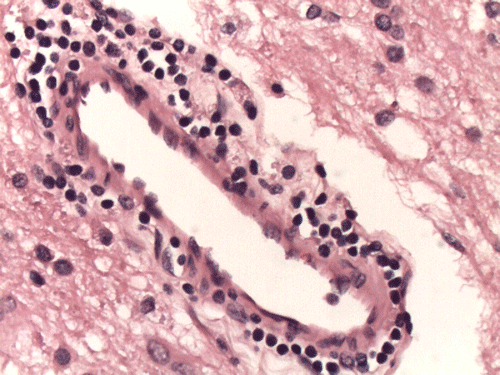

On CT scan, there is multiple hypodense white matter lesions that appear to spare a thin layer of subventricular white matter (Panel A). The T2-weighted images on MRI provides a more accurate estimation. The white matter in the occipital lobes is most affected (Panel A). There is extensive vacuolar changes in the white matter (Panel B and C) and there is a questionable increase in cellularity. In some of the thin walled blood vessels, there is a thin layer of perivascular lymphocytic infiltration which is free of atypia (Panel D, E, and F). The lymphocytes do not appear to extends into the parenchyma. On higher magnification, some large reactive astrocytes can be seen (Panel G). In a minority of areas, some concentric rings can be seen on hematoxylin-eosin stained sections (Panel H). These rings appear to be alternating rings of myelinated and demyelinated white matter and the vacuolar changes appear to be limited mainly to the concentric lesions. The adjacent myelinated areas are spared (Panel I). In some areas, the level of myelin loss appears to be proportional to the level of vacuolar changes (Panel J and K). On immunohistochemistry for glial fibrillary acidic protein (GFAP), the degree of gliosis is also more impressive in areas with more prominent vacuolar changes (Panel L and M). The vacuolar areas also appear to have a reduced density of axons (Panel N). Axonal spheroids are also present in these areas (Panel O). Although a prominent infiltration of foamy histiocytes is not noted on hematoxylin-eosin stains, immunohistochemistry for CD68 illustrated positive cells in a minority of demyelinated areas (Panel P). These cells lacks the foamy nature of macrophages and their morphology would suggest microglial cells. The reactive astrocytes are not immunoreactive for CD68 (Panel Q). Immunohistochemistry for T-cells (CD3) and B-cells (CD20) demonstrates only a thin rim of perivascular infiltration without significant extension into the surrounding parenchyma (Panel R, S, and T).

On histology, there are extensive spongiform degeneration and vacuolar degeneration of the deep white matter associated with variable macrophage, profound axonal loss, degenerating axons with spheroid formation and evidence of axonal injury in adjacent normal appearing white matter  1, 2, 3, 4. Demyelinating changes featured by lost of myelin and infiltration of macrophages have also been described  1,  2, 5,  6. Under the electronic microscope, there are vacuolar degeneration of the oligodendroglia, swollen mitochondria and distended endoplasmic reticulum.